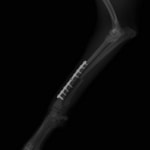

脛骨骨折 : 症例1 | 症例2 | 症例3 | 症例4 | 症例5

当院ではAdvanced Locking plate system(ALPS)と、Locking compression plate system(LCPS)という骨接合法で骨折症例の治療を行っています。

トイプードル 右遠位橈尺骨短斜骨折のALPSによる内固定